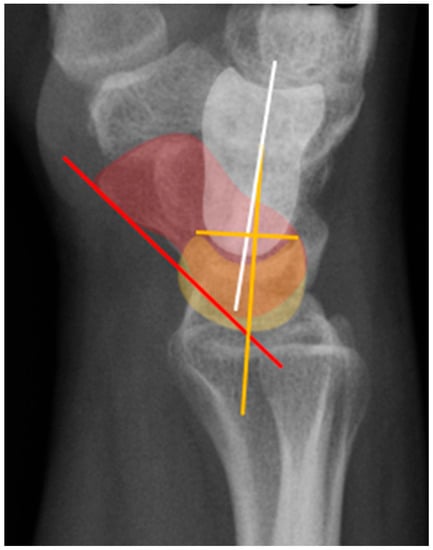

Figure 19. Illustration of the normal carpal alignment and angles. The scapholunate angle is formed between a line drawn along the volar surface of the scaphoid (red line) and a line through the axis of the lunate (yellow line). The capitolunate angle is formed between a line drawn through the axis of the capitate (white line) and a line through the lunate axis (yellow line). Capitate (white), scaphoid (red), lunate (yellow).

The scapholunate angle is formed between a line drawn along the axis or volar surface of the scaphoid and a line through the axis of the lunate, with the normal range being 30–60° (Figure 19) [3]. The capitolunate angle is formed between the lunate axis line and a line through the axis of the capitate, with a normal range of less than 30°, as these should be neutrally aligned (near 0°) in a normal wrist (Figure 19) [6,13].